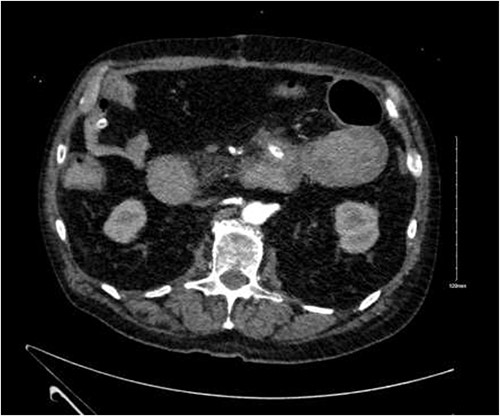

There were no immediate complications to the procedure. The patient returned to intensive care post-operatively. He remained intubated and vital laboratory tests were stabilized. He experienced acute renal failure post-procedure that required haemodialysis and prolonged intubation (Figs 3 and 4).